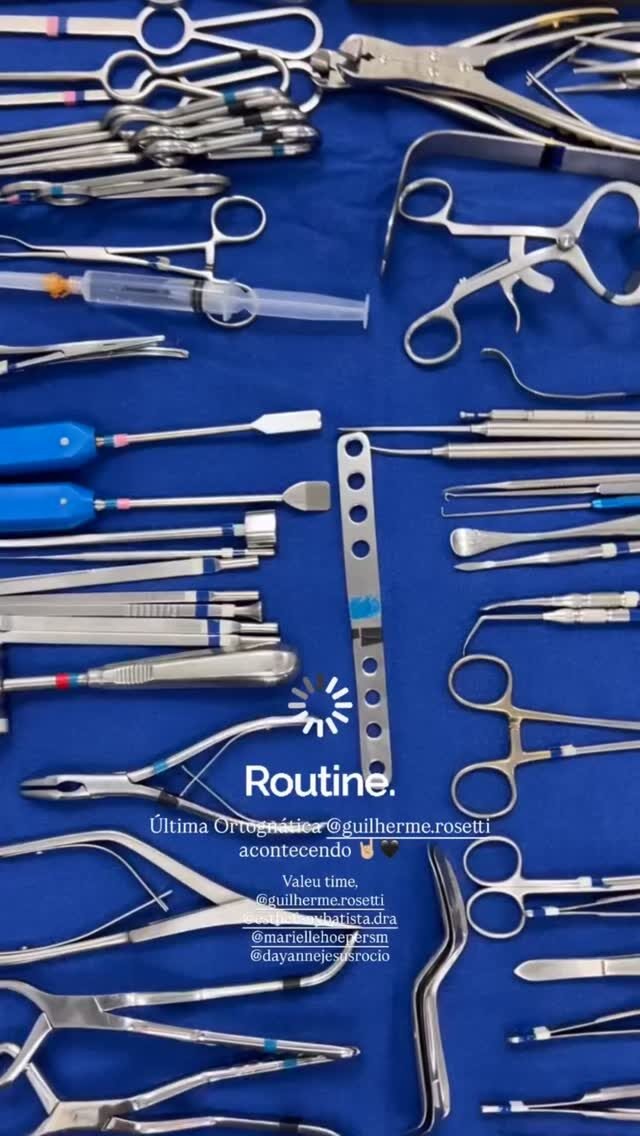

Cirurgia Ortognática

Você sente dificuldade para morder, falar ou até mesmo respirar corretamente? A Cirurgia Ortognática pode ser a solução! Esse procedimento corrige alterações ósseas no maxilar e mandíbula, melhorando a função mastigatória, a harmonia facial e a qualidade de vida.

Etapa I: avaliação (ortodontista + cirurgião)

Etapa II: preparação (ortodontia)

Etapa III: cirurgia

Etapa IV: acompanhamento pós-operatório

Etapa V: acompanhamento